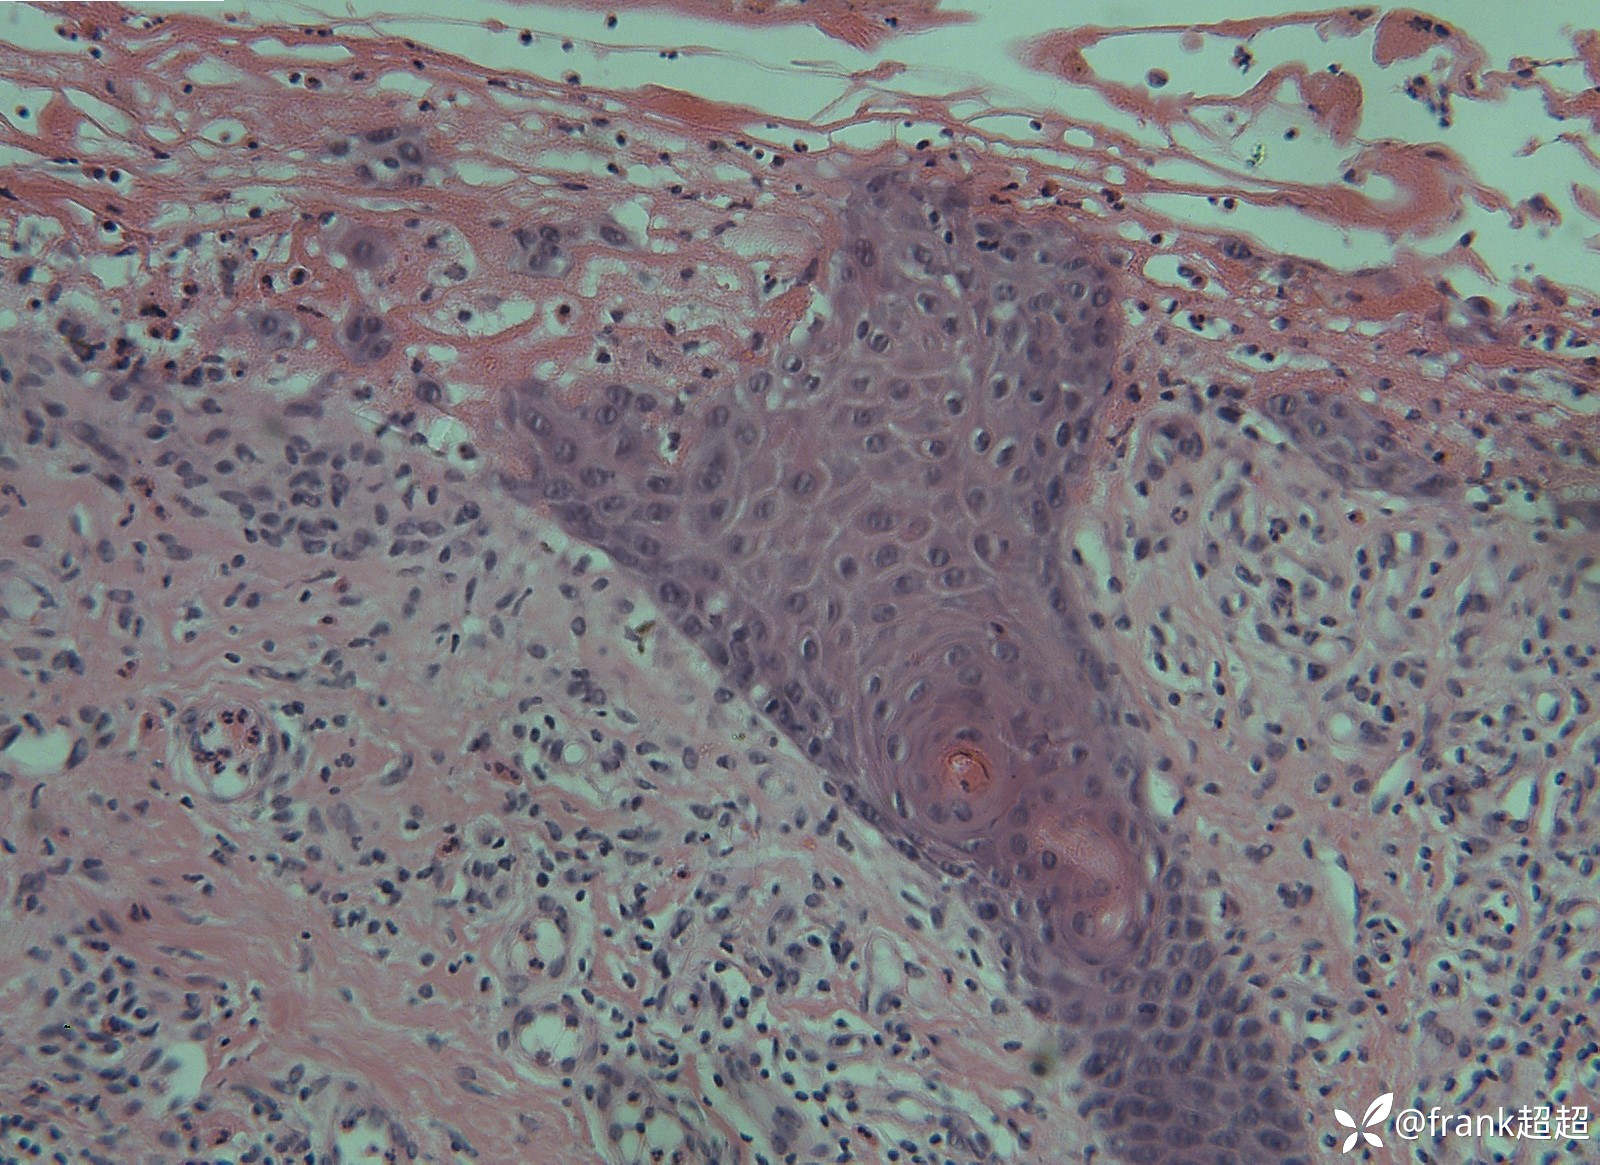

病理:

病理提示:表皮下水疱形成,疱内可见纤维蛋白样物质及少许嗜酸性粒细胞,真皮浅层血管周围可见淋巴细胞及少许嗜酸性粒细胞为主的炎症浸润。